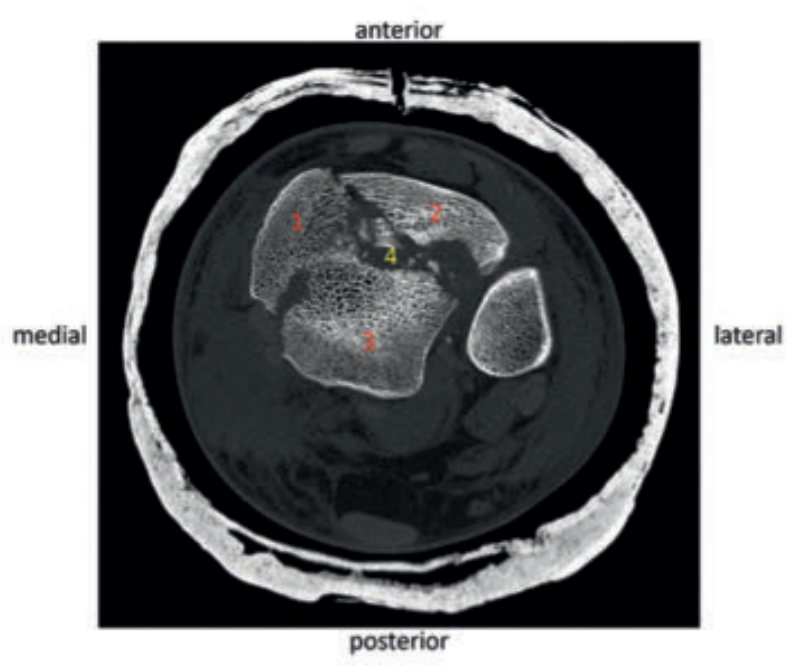

病例1在受伤后送往医院急诊,首先进行了跨踝关节外固定架。尽管患者初始存在Ⅱ度闭合性软组织损伤,但由于及时进行了复位并植入外固定架,未需实施筋膜间室切开术。在术前CT图像中,可清晰观察到3个主要骨折块及1个中央粉碎区。通过及时植入外固定架,可恢复关节位置,并有效避免软组织损伤进一步加重。